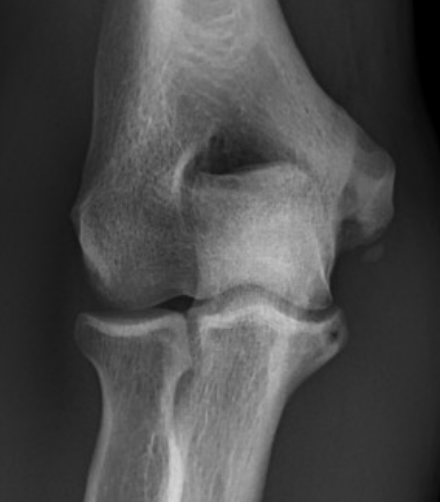

Anatomy of Ulna Collateral Ligament (UCL)

Provides valgus stability

Three components

| Anterior band | Posterior band | Transverse band |

|---|---|---|

|

Most important Stabilizes from 30 - 90 degrees flexion |

Fan shaped Stabilizes from 90 - 120 degrees |

Does not cross elbow joint Does not contribute to vaglus stability |

| Medial epicondyle to sublime tubercle |

Medial epicondyle to medial semilunar notch of ulna |

Medial olecranon to medial coronoid |

Taut band Mean 6 mm thick |

||